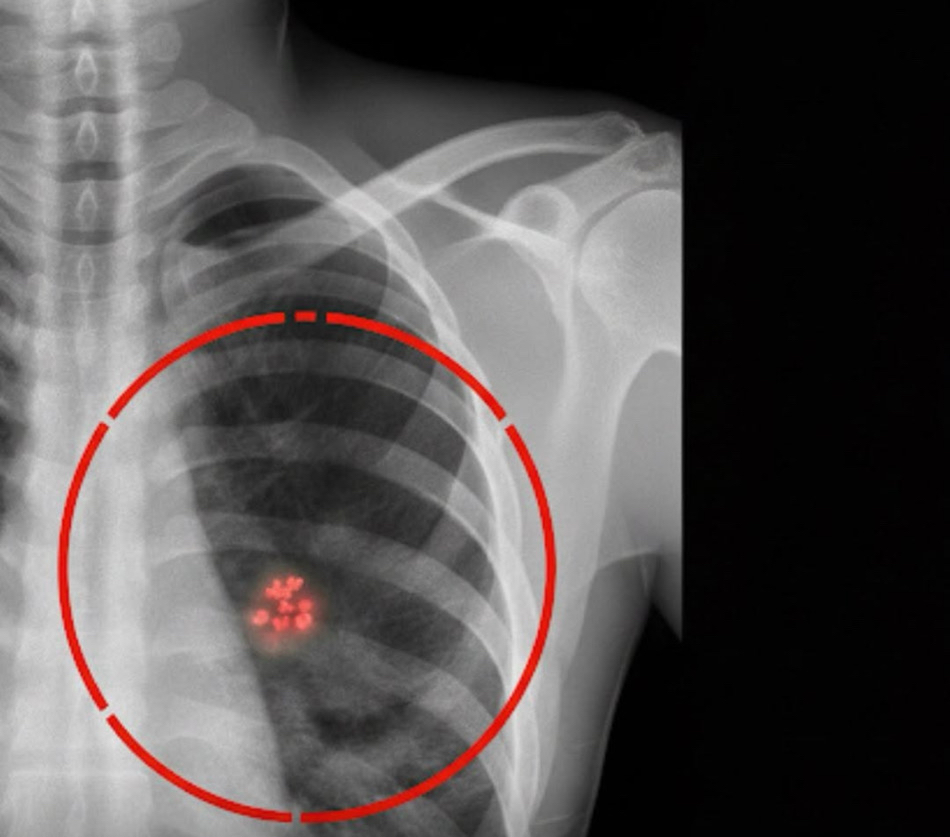

Pesquisas recentes indicam que algoritmos bem calibrados conseguem detectar padrões sutis no tecido mamário pequenas alterações estruturais que escapam ao olhar humano. Esses sinais, embora imperceptíveis em exames convencionais, apontam para uma probabilidade elevada de desenvolvimento do tumor. Com essa previsão antecipada, mulheres de qualquer faixa etária podem receber acompanhamento mais rigoroso, exames periódicos e orientações de saúde com antecedência suficiente para aumentar drasticamente as chances de cura.

A novidade mais significativa: a aprovação de plataformas que transformam mamografia comum em um mapa de risco para os próximos cinco anos. Com isso, a triagem do câncer de mama deixa de ser apenas reativa feita quando um nódulo já é visível e passa a ser proativa e personalizada. Isso não só muda o prognóstico individual, como pode reestruturar a forma como o sistema de saúde aborda a prevenção.

Mas é importante lembrar: a IA não faz diagnóstico. Ela gera um alerta de risco. A confirmação dependerá de exames extras e acompanhamento médico. Mesmo assim, a ferramenta funciona como um sinal de alerta precoce, capaz de mobilizar ações preventivas o que muda o cenário para mulheres que, de outra forma, só seriam acompanhadas anos depois, quando sintomas aparecessem.